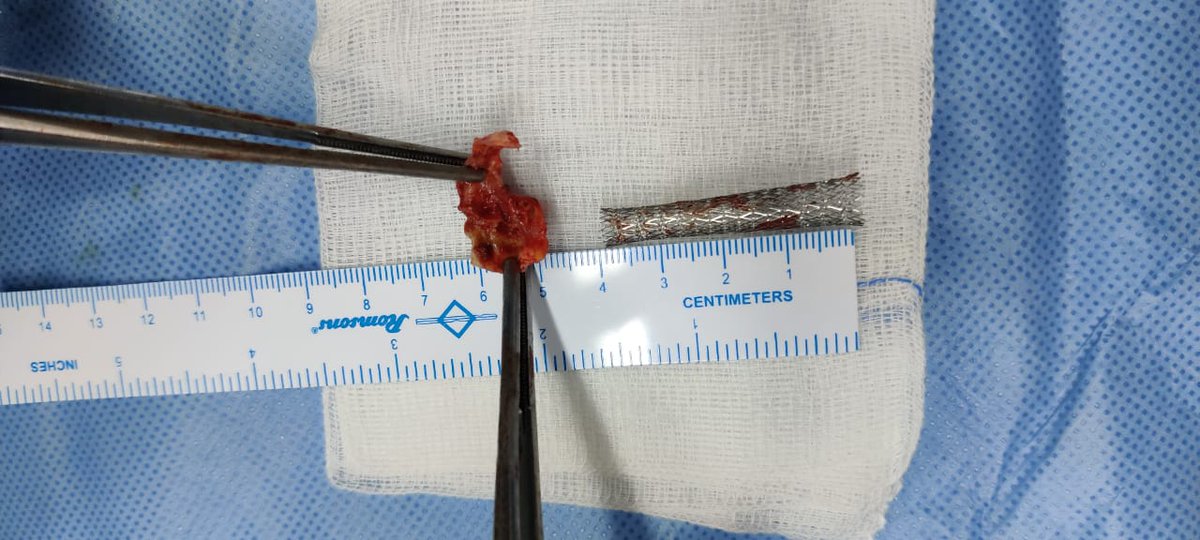

DSA also confirmed the extensive clot. In view of her recent LSCS 20 days ago, we were hesitant about giving IV lytics (urokinase infusion). Hence went in with an ACE 5 Max catheter and sucked out a mountain of clot